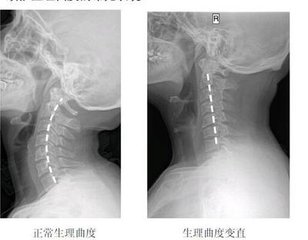

导读: 颈椎生理曲度的存在,能增加颈椎的弹性,减轻和缓冲重力的震荡,防止对脊髓和大脑的损伤。颈椎生理曲度变直多由姿势不当而造成,颈椎曲度变直又称颈椎生理曲度消失或颈椎生理曲度反弓。所以这就要求大家平时特别注意